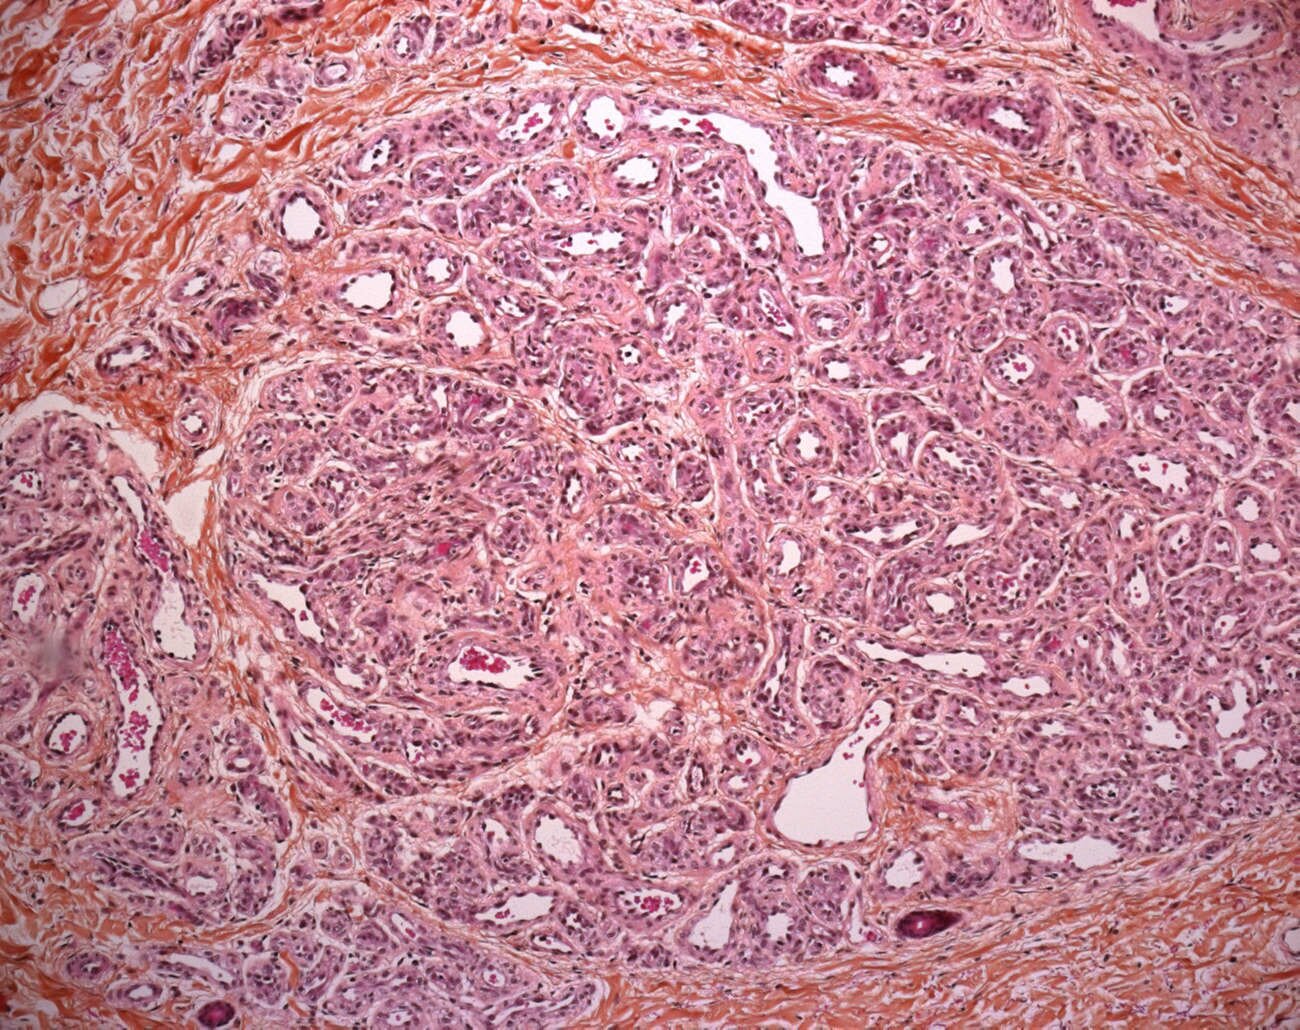

These tumors are highly cellular, involving the dermis, often with extension into the subcutis. The tumor has a lobular architecture and plump endothelial cells. The latter cells express glut-1 antigens throughout the life of this tumor.

proliferative phase